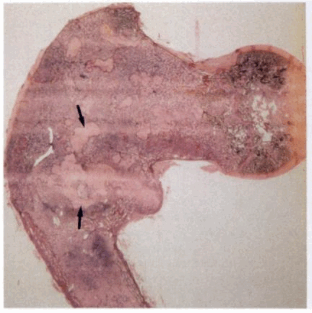

3. Макроскопические и хирургические особенности:

• Объемное образование от бежево-желтого до белого цвета

• Эластичная или зернистая консистенция, в зависимости от фиброзного или костного содержимого

• Фиброзная ткань, содержащая отдельные трабекулы незрелой грубоволокнистой кости, напоминающие китайские иероглифы

Макроскопические изменения

- При макроскопическом исследовании определяются беловато-красные опухолевые очаги разной плотности, в зависимости от степени выраженности их минерализации. Имеются многочисленные кисты, заполненные желтоватой или красноватой жидкостью, и полупрозрачные участки хряща до 3 см в диаметре.

Микроскопические изменения

- Многочисленные остеоидные балки неправильной формы, лежащие в фиброзной ткани с небольшим числом остеобластов. Остеоидные балки представляют собой большей частью волокнистую, но не компактную кость.

- Мелкие участки остеоида могут быть обызвествлены. Известь откладывается, как правило, в центре балки. Имеются многоядерные клетки типа остеокластов, окаймляющие некоторые балки.

- Однородная склеротическая фиброзная дисплазия (ФД) (23-34%)3. Макроскопические и хирургические особенности:

• Фиброзная ткань, имеющая «песчаную» структуру и цвет от желтовато-коричневого до серого

• Вариабельная консистенция, которая зависит от фиброзного и костного компонентов

• Грубоволокнистая костная ткань незрелая, непрочная, склонна к переломам

• Могут присутствовать геморрагические, кистозные изменения4. Микроскопия:

• Фиброзная строма, обычно бессосудистая, низкая целлюлярность

• Метаплазия костей: костные трабекулы, состоящие из незрелой, грубоволокнистой костной ткани, которые выглядят как фигуры необычной формы, «плавающие» в фиброзной строме